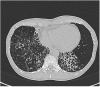

Non-tuberculous mycobacteria (NTM) are ubiquitous environmental organisms that may cause opportunistic infections in susceptible hosts. Lung infections in immunocompetent persons with structural lung disease are most common, while disseminated disease occurs primarily in immunocompromised individuals. Human disease caused by certain species, such as Mycobacterium avium complex, Mycobacterium abscessus, and Mycobacterium kansasii, is increasing in incidence and varies by geographic distribution. The spectrum of NTM disease varies widely in presentation and clinical outcome, but certain patterns can be organized into clinical phenotypes. Treatment options are limited, lengthy, and often toxic. The purpose of this case-based review is to provide non-clinician scientists with a better understanding of human NTM disease with an aim to stimulate more research and development.